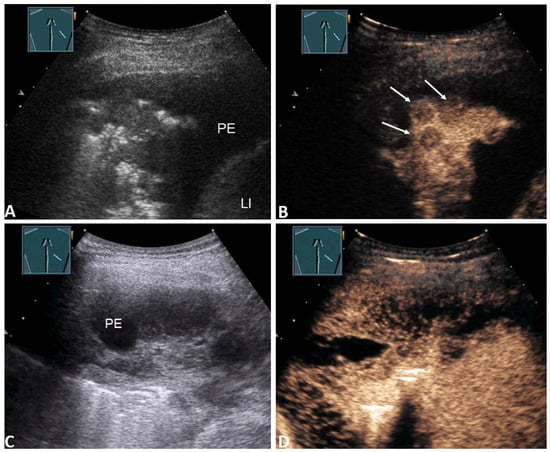

| Enhancement of septa or solid formation (Figure 4D) | 2 (2.4%) | 2 (4.8%) | 0 (0.0%) | 0.494 * |

| No enhancement of septa or solid formation (Figure 5C) | 81 (97.6%) | 40 (95.2%) | 41(100.0%) | |

| Inhomogeneous enhancement of lung consolidation (Figure 5B–D) | 25 (30.1%) | 19 (45.2%) | 6 (14.6%) | 0.004 * |

| Homogeneous enhancement of lung consolidation | 58 (69.9%) | 23 (54.8%) | 35 (85.4%) | |